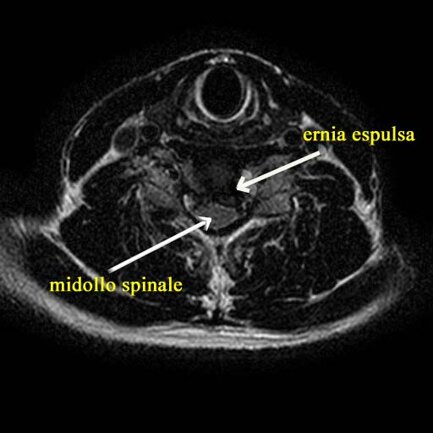

Una risonanza lombare ha ernia discale cervicale C5-C6 .

Nel corso delle sedute (effettuate alcune con tecnica ecoguidata iuxtaradicolare C5-C6, utilizzo di ecosonordoppler vascolare, graduale diminuzione del dolore.

Alla fine delle 8 sedute (4 settimane di trattamento), regressione completa del dolore brachiale sinistro, con possibilità completa di mobilizzazione e graduale ritorno alla normalità e ripresa dell’attività lavorativa, senza assumere alcun farmaco.